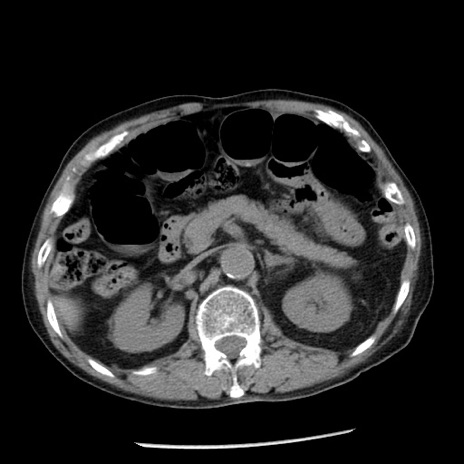

冠状断像

【症例】80歳代男性

【主訴】嘔吐

【現病歴】昨晩2回嘔吐あり、今朝になっても嘔吐あり。来院。

【既往歴】胃潰瘍

【身体所見】意識清明、BT 37.6℃、BP 166/95mmHg、HR 100bpm、SpO2 97%、腹部:平坦・軟、腸蠕動音聴取良好、圧痛なし。

【データ】WBC 21900、CRP 1.46